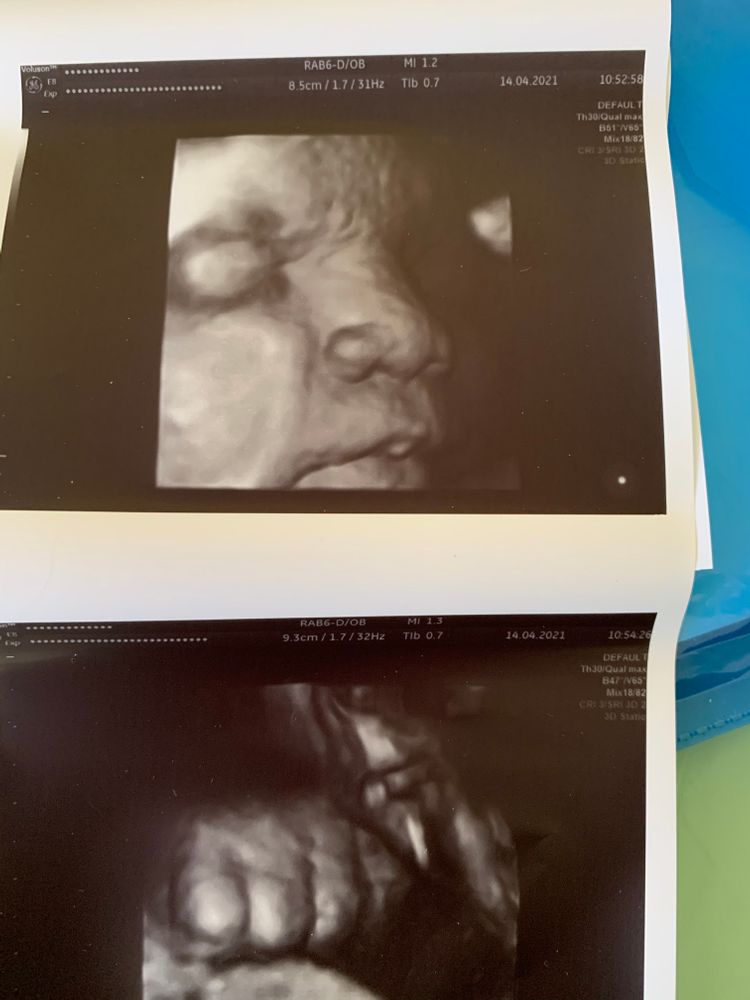

Третий скрининг

Были на узи. Сегодня 30 недель и 5 дней. Все у нас хорошо. Опережаем срок, по весу дочка сейчас на 33 недели - 2020 гр.

плацента первой степени, что нормально для срока, доплер хороший. Пессарий стоит на месте, шейка 24 мм. Отлично!